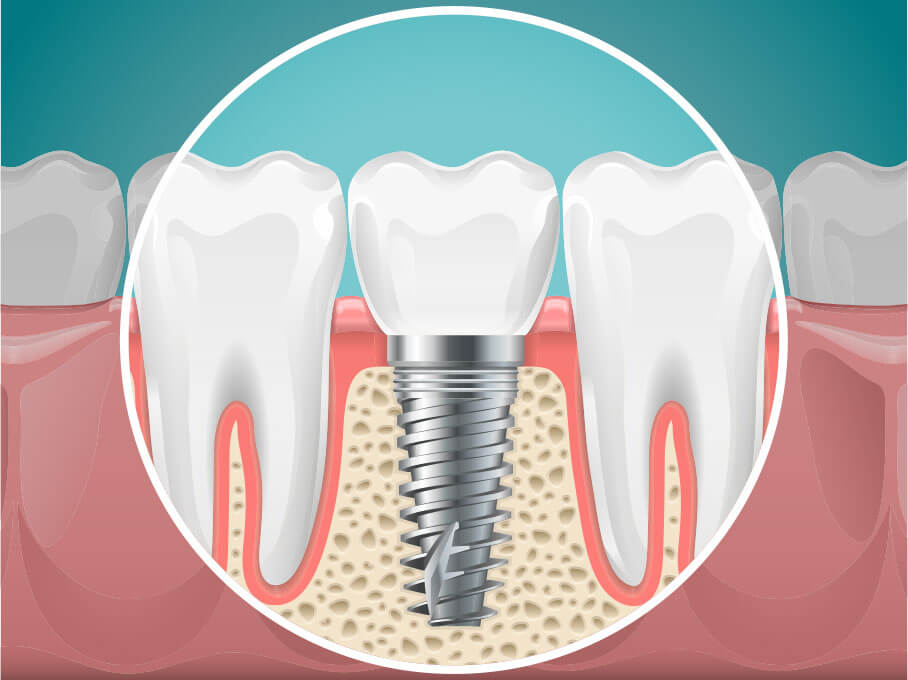

インプラント治療は

土台となる歯周の健康が大切です

顎骨に人工歯根を埋め込む外科処置が必要なインプラント治療には、精密な診断・手術が求められます。また手術が成功しても、土台となる歯周組織や顎骨が健康でないとインプラントが安定せず、長期間の使用が困難です。

当院では歯周病専門医が事前に歯周の状態を確認し、歯周病の場合はその治療をしたうえでインプラント治療に進みます。